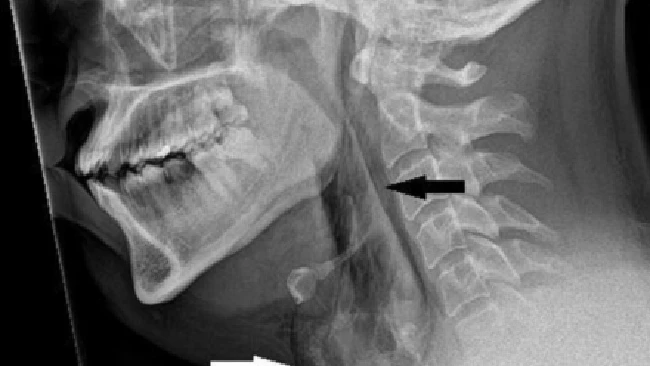

Foto: BMJ Case Reports

Pria itu dilarikan ke Ninewells Hospital di Dundee karena merasakan nyeri hebat setelah menahan bersin. Hasil pemeriksaan CT scan menemukan adanya sobekan kecil berukuran 2 mm pada bagian tenggorokannya.

Kasus ini dicatat dalam jurnal medis BMJ Case Reports. Ketika diperiksa, dokter mendengar suara seperti retakan saat memegang leher pasien dan menemukan bahwa ia mengalami kesulitan mengendalikan gerakan leher. Pria itu mengalami kejadian tersebut saat sedang mengemudi.